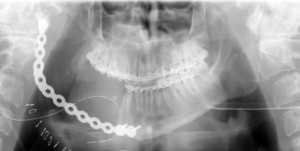

Wir führten zunächst eine Zystektomie in Intubationsnarkose unter Erhalt des N. alveolaris inferior durch. Die histologische Untersuchung ergab ein Ameloblastom. Daraufhin erfolgte eine Hemimandibulektomie rechts von extraoral mit Erhalt des rechten Unterkieferköpfchens und Überbrückung des Defektes mit einer Rekonstruktionsplatte. (Abbildung 4). Histologisch fanden sich intraossär und in der anteilig resezierten Mundschleimhaut weitere Ausläufer des Tumors. Die Resektionsränder waren tumorfrei.

Drei Monate Später wurde die rechte Unterkieferhälfte mit einem freien Rippen- und Beckenkammtransplantat rekonstruiert.